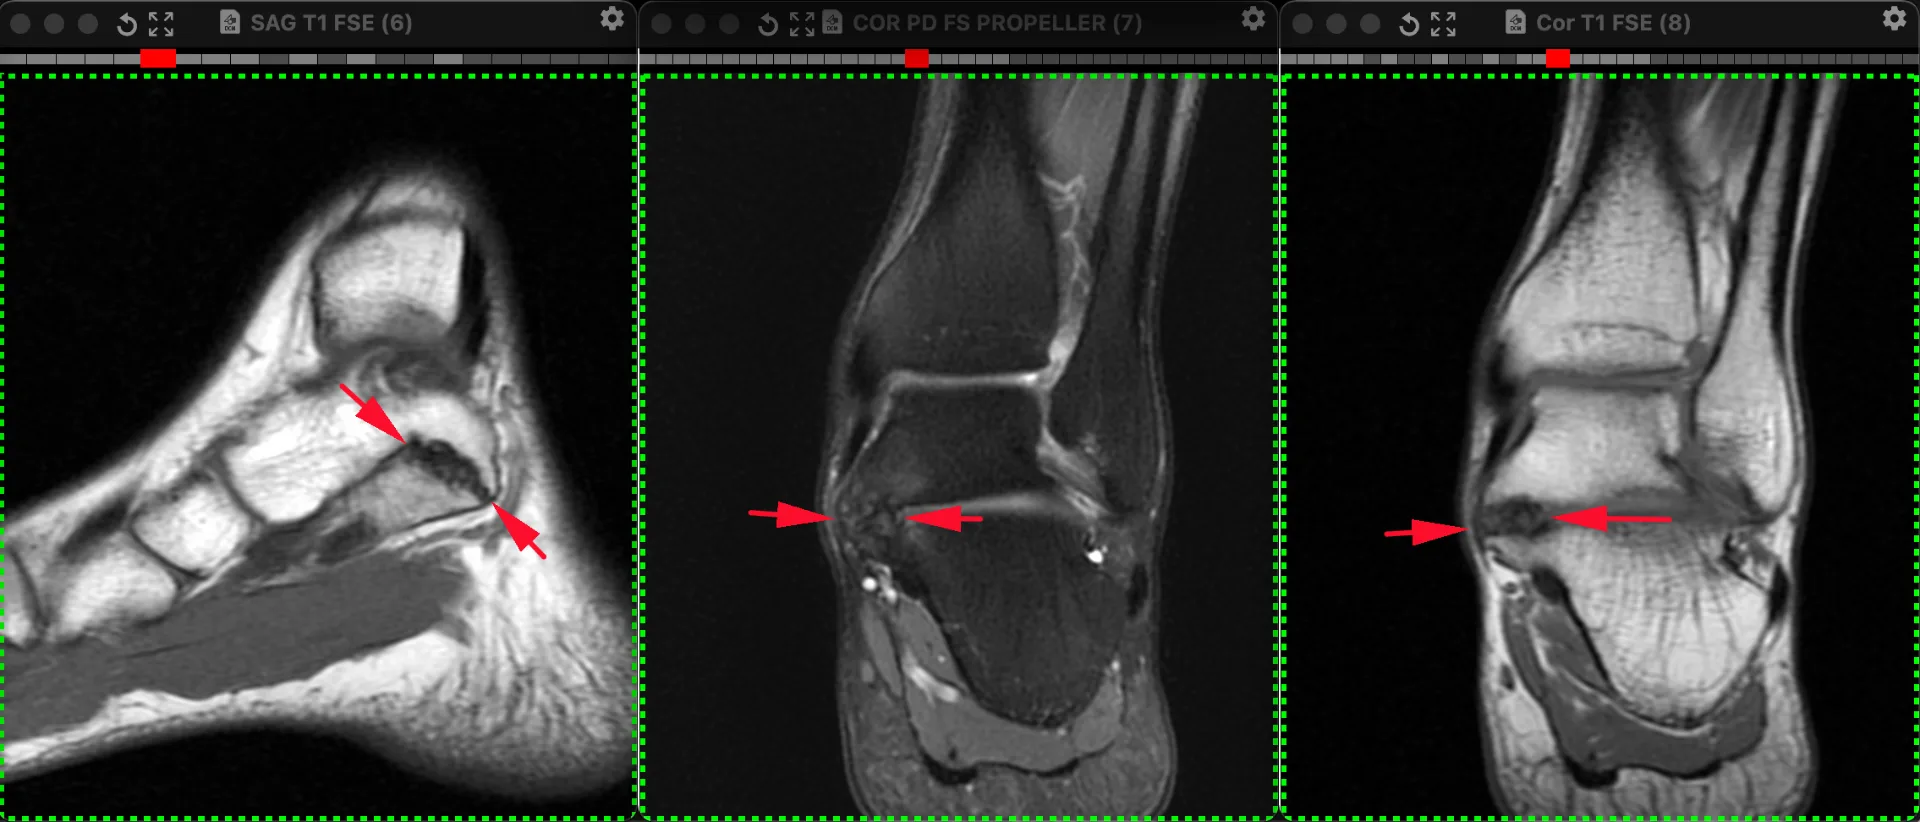

Один из вариантов тарзальной коалиции: таранно-пяточный синдесмоз. Напомню, что тарзальной называется патологическое сочленение между костями плюсны и предплюсны, может быть в виде синостоза, синхондроза и синдесмоза. Если имеется синдесмоз (как здесь), то хроническая его перегрузка приводит к артрозу и всем его типичным проявлениям, как здесь: неровностям контактных поверхностпей, субхондральные отёк и полости (кисты). Локально болит, особенно при нагрузке. Пациент 26 лет.